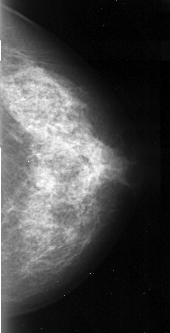

A_1104_1.RIGHT_MLO

RIGHT_MLO LINES 5146 PIXELS_PER_LINE 2491 BITS_PER_PIXEL 16 RESOLUTION 42 NON_OVERLAY